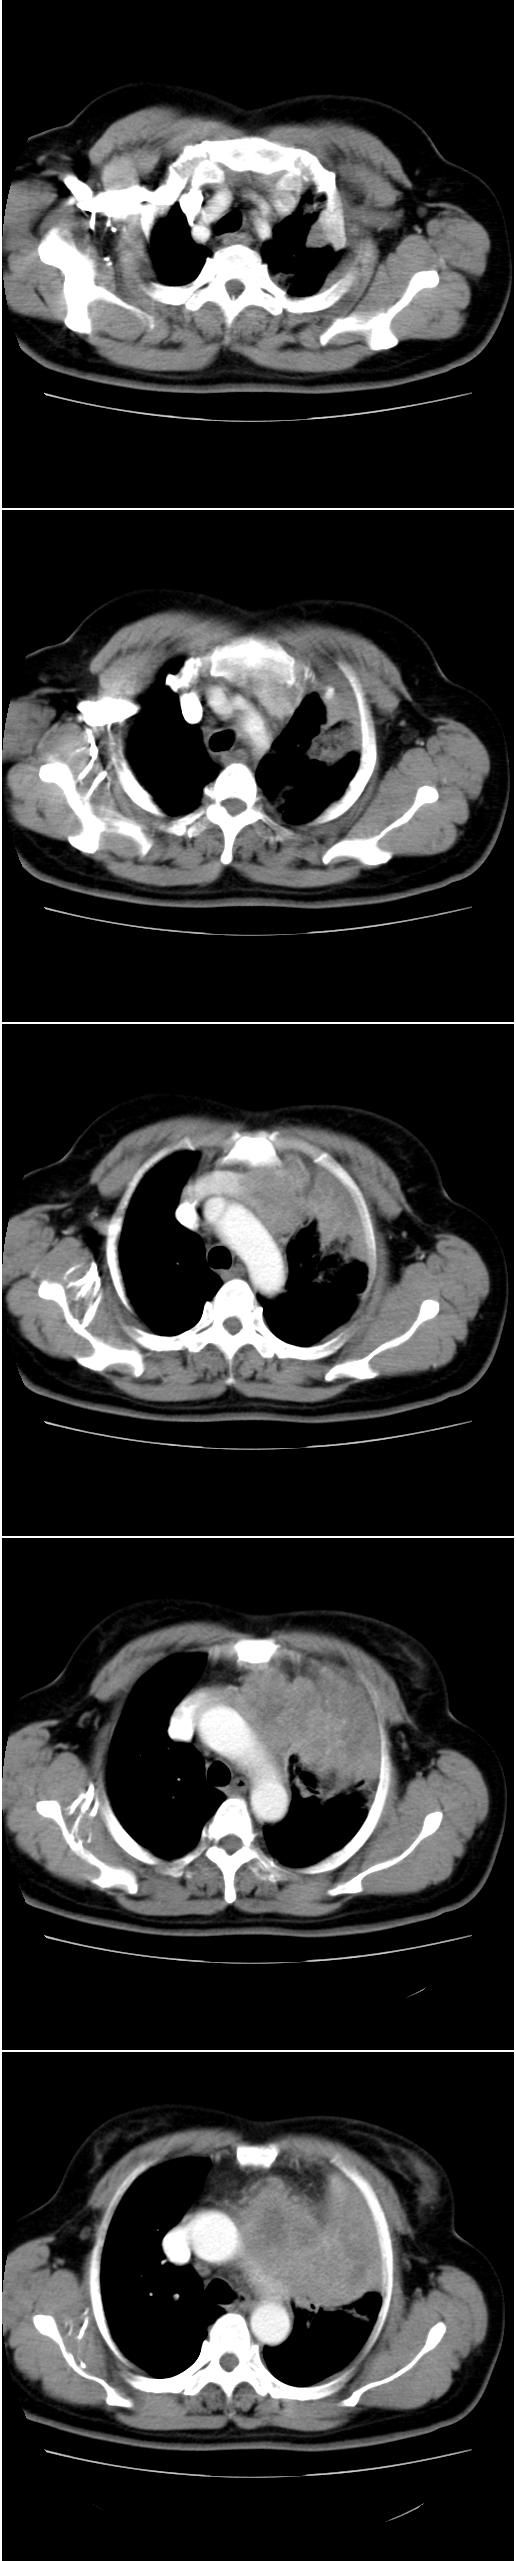

标题: CT13028:女,56岁。咳嗽、气促一月,咳血一周。CT值增加约30 [打印本页]

标题: CT13028:女,56岁。咳嗽、气促一月,咳血一周。CT值增加约30

考虑左上肺癌(周围型)伴左肺门及纵隔转移(主肺动脉窗旁病灶可能为肿大并坏死的淋巴结),不除外纵隔型肺癌

肺癌并纵隔,左肺门侵犯,纵隔多发肿大淋巴结

支持纵隔旁型肺癌伴主动脉弓\\主肺动脉及左侧头壁动脉受侵.

考虑左肺中心性肺癌并纵隔淋巴结转移,累及左肺动脉及左侧头臂静脉.但不除外纵隔恶性肿瘤累及肺组织.

考虑左侧中央型肺癌伴左肺上叶肺不张及前纵隔淋巴转移。

1)考虑为:左肺上叶中心型肺癌伴左肺上叶阻塞性肺炎、节段性肺不张,左肺门及纵隔淋巴结转移。2)左侧少量胸腔积液。